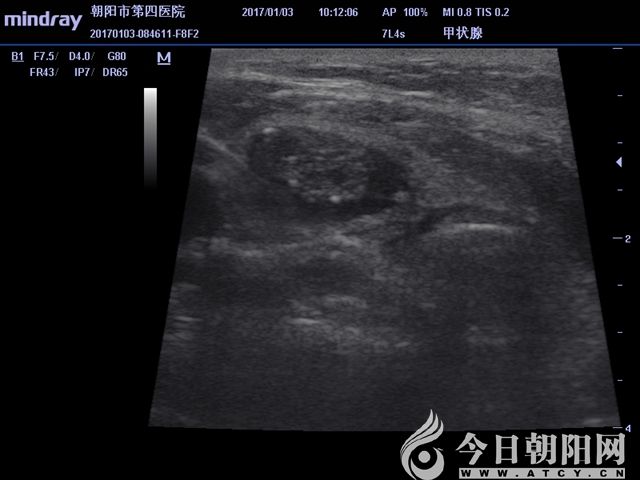

超聲顯示囊實(shí)結(jié)合性病變

患者為65歲女性,發(fā)現(xiàn)左右側(cè)頸部包塊1個(gè)月,通過(guò)超聲檢查考慮甲狀腺腺瘤伴出血。患者從心理上不能接受頸部手術(shù)后切口瘢痕,拒絕手術(shù)切除,要求微創(chuàng)治療。針對(duì)患者要求,該院外科團(tuán)隊(duì)為其設(shè)計(jì)了治療方案——行甲狀腺微波消融術(shù)。手術(shù)采用局麻,在超聲影像引導(dǎo)下,順利準(zhǔn)確穿刺,抽出積血后,再于實(shí)性病變處用活檢針穿刺取病理,證實(shí)良性病變。